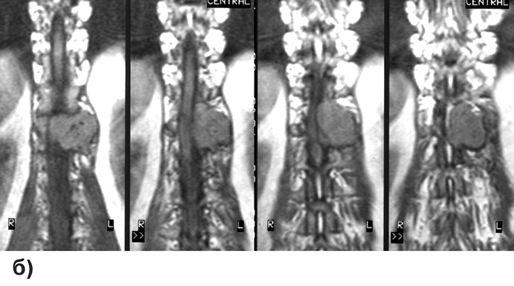

Диагностика основывается на данных МРТ (рис. 4), для оценки костных изменений обычно производятся спондиллограммы и КТ. Для принятия решения об оптимальной тактике лечения необходима верификация степени распространения онкологического процесса, включающая радиоизотопное сканирование костей скелета, рентгеновское (включая КТ) и/или УЗИ щитовидной железы, органов грудной клетки, брюшной полости, забрюшинного пространства и малого таза.

Рисунок 4. Метастаз аденокарциномы в 12 грудной позвонок, вызывающий компрессию дурального мешка. МРТ с контрастным усилением:

а — Т1-взвешенные изображения, сагиттальная проекция; б — Т2-взвешенные изображения, фронтальная проекция